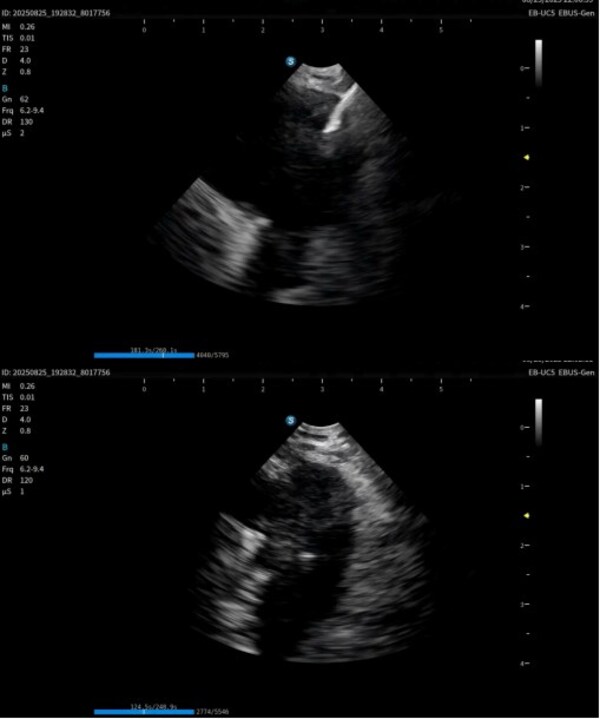

作为在呼吸诊疗领域的重磅产品,本次在产品创新设计上和工艺技术上取得了重大突破,显著提升了光学图像和超声图像的质量,同时镜体保持了良好的操作性,在钳镜比和视野角综合参数可达到全球同类产品最佳性能。目前在临床应用表现突出,取得了专家的认可和好评。

超声电子支气管内窥镜凭借其"微创、精准、安全"的特点,已成为呼吸介入领域的核心技术之一。开立医疗全系列产品全面上市可为肺部肿瘤、纵隔病变提供管内清晰光学影像,管外高清声学断层组织及血流影像,提供精准可视化介入操作,为疾病的诊断提供更精准、更安全、更高效的一体化诊疗解决方案。